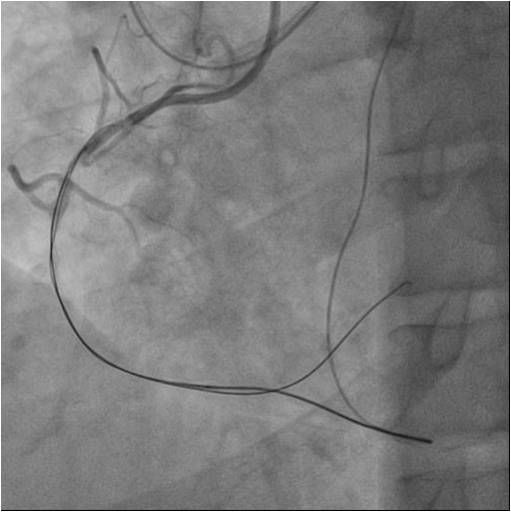

Numerousattempts of antegraderecanalization using guidewires of different stiffnesswere unsuccessful. Pts ofretrograde recanalization using guidewires of different stiffnesswereunsuccessful. Another attempt at antegraderecanalization led to dissection dista RCA. Retrograde recanalization was performed using the technique of «kissing-wire». retrograde guidewire was inserted into theproximal segment of the RCA. Guidewire was externalized into the guide catheterusing Reverse CART technique. The tip-in technique was used for the Corsairantegrade microcatheter over the retrograde wire. Tthe microcatheterwassuccessfully inserted into the distal segment of the RCA. A soft antegradeguidewire was placed. A balloon catheter 2.0x30 mm was used for predilation inthe proximal middle and distal segments of the RCA at 14 atm. Consecutive DES2.75x44mm, DES 2.75x44mm, DES 3.5x39 mm stents were implanted in the distal,middle and proximal segments of the RCA, at pressures up to 16 atm.